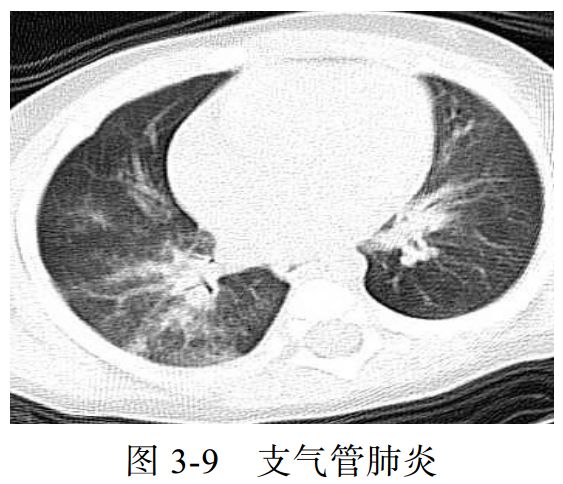

(二)支气管肺炎

支气管肺炎又称为小叶性肺炎,常见于婴幼儿和年老体弱者。

致病菌主要为肺炎链球菌、金黄色葡萄球菌,常可为麻疹、百日咳、流感的并发症。

病变以小叶支气管为中心,在支气管和肺泡内产生炎性渗出。

临床表现为畏寒发热、胸痛、咳嗽、咳痰、呼吸困难等。

影像学表现:

(1)病变多分布于两肺中内带,可见沿支气管血管束分布的斑片、絮片、条索状影(图 3-9),出现树芽征。

(2)病灶可融合成团片状,常伴有局限性肺气肿、肺不张。